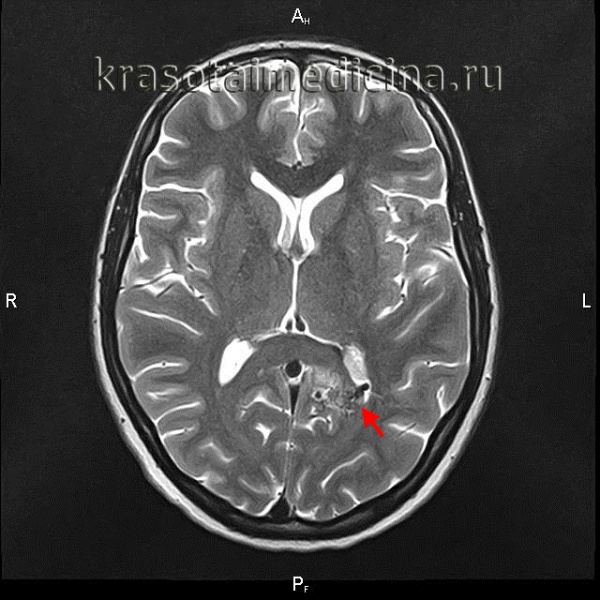

Артериовенозные мальформации головного мозга — врожденные аномалии церебральных сосудов, характеризующиеся образованием локального сосудистого конгломерата, в котором отсутствуют капиллярные сосуды, а артерии напрямую переходят в вены. Артериовенозные мальформации головного мозга проявляются упорными головными болями, эпилептическим синдромом, интракраниальным кровотечением при разрыве сосудов мальформации. Диагностика осуществляется при помощи КТ и МРТ сосудов головного мозга. Лечение хирургическое: транскраниальное иссечение, радиохирургическое вмешательство, эндоваскулярная эмболизация или комбинация этих методик.

Артериовенозные мальформации головного мозга (церебральные АВМ) — измененные участки церебральной сосудистой сети, на которых вместо капилляров имеются многочисленные разветвления извитых артерий и вен, формирующих единый сосудистый конгломерат, или клубок. АВМ относятся к сосудистым аномалиям развития головного мозга. Встречаются у 2 человек из 100 тыс. населения. В большинстве случаев клинически дебютируют в период от 20 до 40 лет, в отдельных случаях — у лиц старше 50 лет. Артерии, формирующие АВМ, имеют истонченные стенки с недоразвитым мышечным слоем. Это обуславливает главную опасность сосудистых мальформаций — возможность их разрыва.

Церебральные артериовенозные мальформации могут располагаться в любом месте головного мозга: как на его поверхности, так и в глубине. В месте локализации АВМ отсутствует капиллярная сеть, циркулирование крови происходит из артерий в вены напрямую, что обуславливает повышенное давление и расширение вен. При этом сброс крови в обход капиллярной сети может повлечь за собой ухудшение кровоснабжения церебральных тканей в месте расположения АВМ, приводя к хронической локальной ишемии мозга.

Поводом для обращения к неврологу до разрыва АВМ могут быть упорные головные боли, впервые возникший эпиприступ, появление очаговой симптоматики. Пациенту проводится плановое обследование, включающее ЭЭГ, Эхо-ЭГ и РЭГ. При разрыве АВМ диагностика осуществляется в экстренном порядке. Наиболее информативны в диагностике сосудистых мальформаций томографические методы. Компьютерная томография и магнитно-резонансная томография могут быть использованы как для визуализации тканей мозга, так и для исследования сосудов. В случае разрыва АВМ МРТ головного мозга более информативно, чем КТ. Она дает возможность выявить локализацию и размер кровоизлияния, отдифференцировать его от других объемных интракраниальных образований (хронической гематомы, опухоли, абсцесса головного мозга, церебральной кисты).

При торпидном течении АВМ МРТ и КТ головного мозга могут оставаться в норме. Обнаружить сосудистую мальформацию в таких случаях позволяет лишь церебральная ангиография и ее современные аналоги — КТ сосудов и МР-ангиография. Исследования церебральных сосудов проводятся с использованием контрастных веществ. Диагностика осуществляется нейрохирургом, который также оценивает операционный риск и целесообразность хирургического лечения АВМ. При этом следует учитывать, что при разрыве, в связи с компрессией сосудов в условиях гематомы и отека мозга, томографический размер АВМ может быть существенно меньше реального.